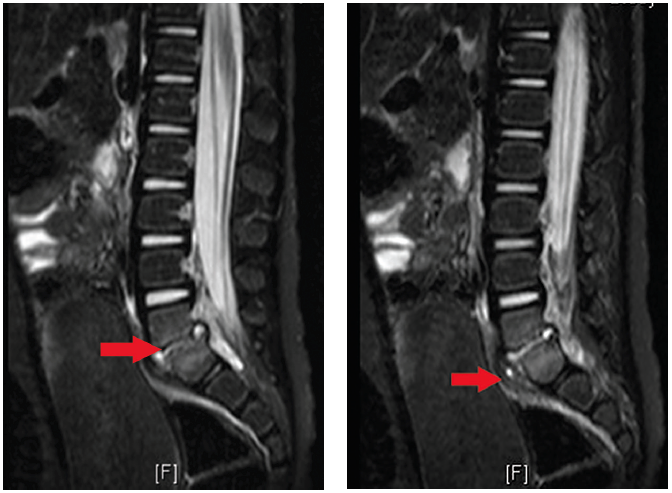

Figure 1. Decreased disc space with bony erosions of the endplates of L5-S1 (arrow).

Figure 2. Perivertebral soft tissue swelling, consistent with a phlegmon (arrow).

The MRI of the spine (Figure 1) demonstrated an abnormal signal intensity in the lower aspect of L5 and the upper aspect of the S1 vertebral body, which was irregular and had erosion of the endplates. An abnormal signal intensity in the L5-S1 disc space with prevertebral soft tissue swelling was suggestive of phlegmon (Figure 2). A small fluid collection suggestive of an abscess was seen in the prevertebral space, measuring approximately 3 mm x 6 mm.

There was some abnormal signal intensity in the epidural space posterior to L5-S1 level, which was suggestive of a phlegmon. There was a small amount of fluid posterior to the L5-S1 disc space measuring approximately 2 mm x 3 mm, which likely represented a tiny abscess.

Finally, there was enhancement of the phlegmon on the postcontrast T1 images.